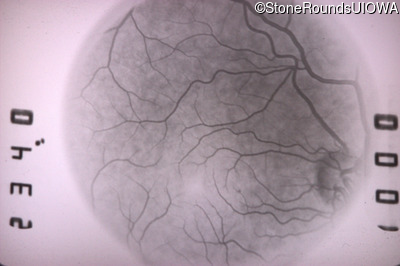

Goldmann Visual Field - Right - 20/25 +2 sc

Exemplar

Goldmann Visual Field - Left - 20/20 -1 sc